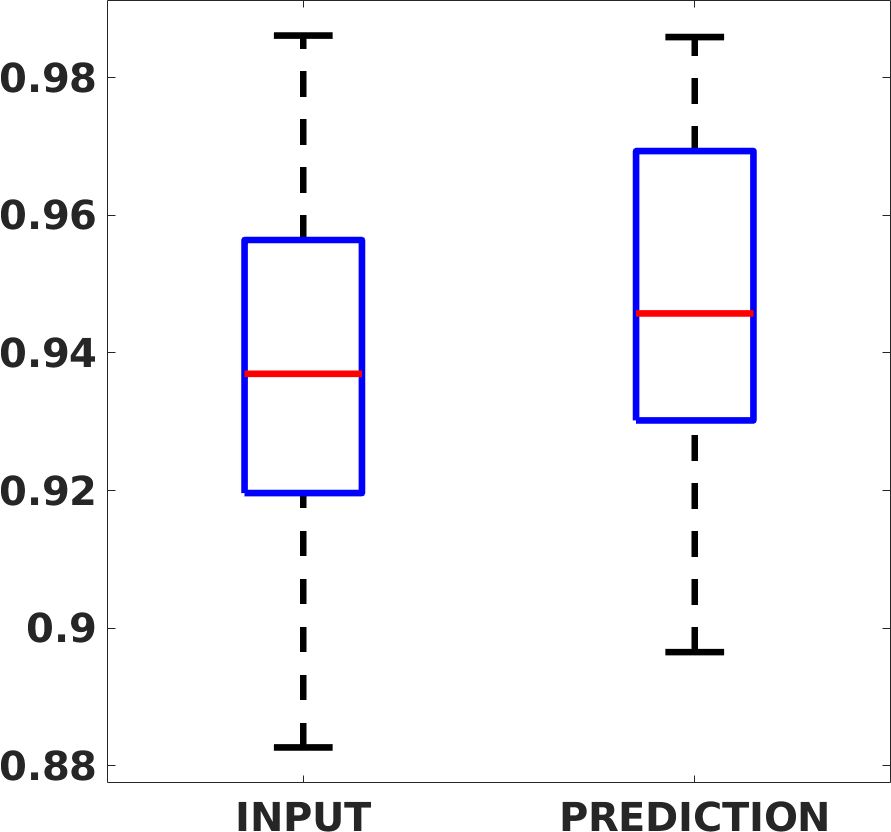

Fig. 7(a-b-c, left) shows the box plot of the statistics of the PSNR on three different anatomical districts, comparing the target images with the prediction and the cubic convolution, respectively. The metrics are computed on a data set of 200 images of the same district and with the same up-sampling factor. We report that the PSNR median value improves of on obstetric 2X raw images, on cardiac 2X raw images, and on abdominal raw 4X images.

Fig. 7(a-b-c, right) shows the histogram of the absolute value of the error with respect to the target image, of the prediction and Cubic convolution results, respectively. The histograms show the number of pixels where the prediction error is lower than 5 (i.e., the first bin of the histogram), which means very similar to the target when visually analysing the images. From the Cubic convolution to the predicted images, this value increases of on obstetric 4X raw images, on cardiac 4X raw images, and on abdominal 4X raw images.

Fig. 17 (left) shows the box plot of the quantitative metrics, comparing the target images with the prediction and the Cubic convolution, respectively. The PSNR metric is computed on a data set of 200 images, belonging to the same district, and with the same up-sampling factor. Analysing the obstetric anatomical district and concerning the corresponding raw images (Fig. 7 (a, left)), the denoising allows the network to significantly improve the results of the up-sampling and the prediction. In particular, comparing the target images with the predicted images, the median PSNR value of obstetric 2X denoised images is 51.8, compared to the median PSNR value of obstetric 2X raw images which is 36.9.

Fig. 17 (right) shows the histogram of the absolute value of the error with respect to the target, of the prediction and Cubic convolution respectively. This result shows that our framework increase of and (2X and 4X, respectively) the number of pixels where the prediction error is lower than 5, which is very similar to the target when visually analysing the images, and improved with respect to the learning framework applied to raw images. According to Fig. 18, our method improves the accuracy of Cubic convolution. For example, the SSIM increases of on cardiac 2X and the MAE increases of on abdominal 4X.